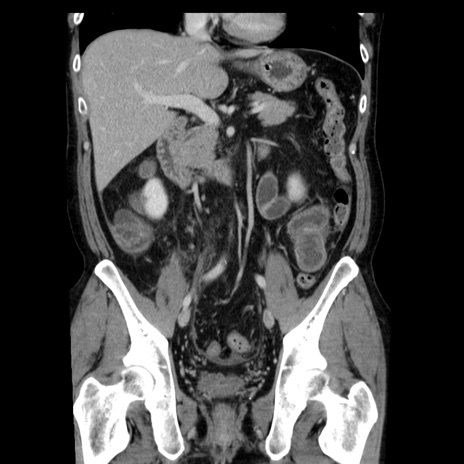

横断像

【症例】40歳代男性

【現病歴】2日前から胃痛あり。徐々に周期的な激痛に変化した。本日になっても激痛があるため受診。

【身体所見】意識清明、BT 38-39℃台あり、腹部:膨満、やや硬、右下腹部に圧痛あり。

【データ】WBC 8500、CRP 23.26